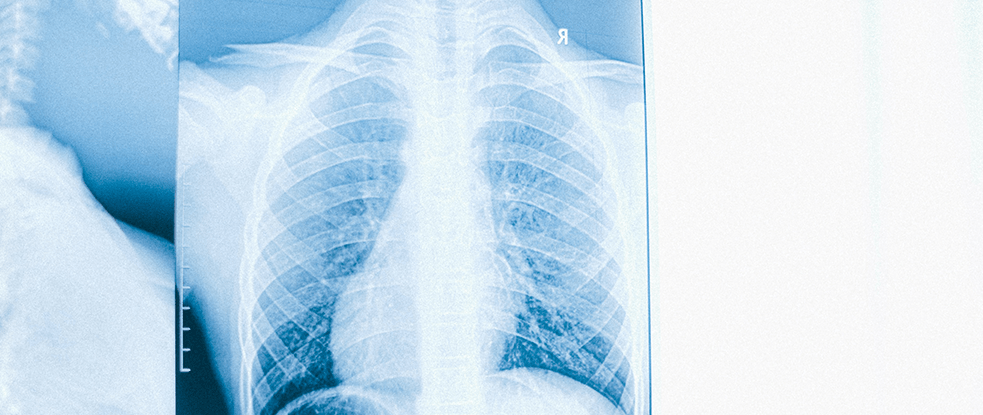

Câncer de Pulmão

O câncer de pulmão é um grave problema de saúde pública, com alta incidência, mortalidade e fatores de risco conhecidos, já que a maioria destes tumores acomete fumantes. A grande novidade é que a oncologia torácica se desenvolveu acima das expectativas nos últimos anos, e a queda de mortalidade por câncer em geral se deve, principalmente, à queda da mortalidade por câncer do pulmão. É certo, portanto, que tivemos extraordinários avanços na compreensão e nos cuidados oferecidos aos que sofrem dessa doença.